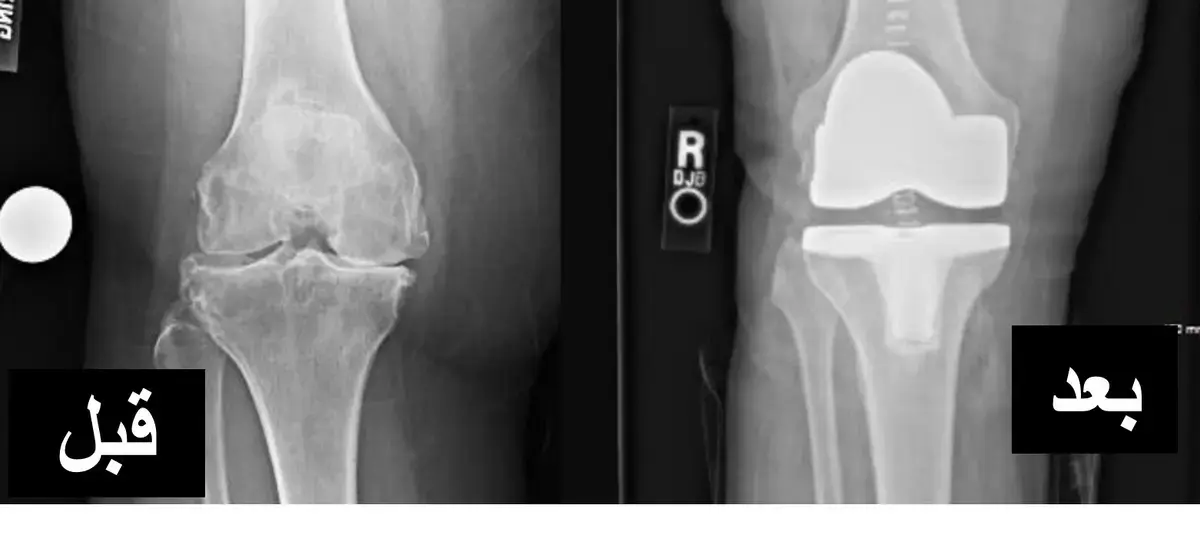

* جراحات استبدال المفاصل (Arthroplasty): في حالات التلف الشديد للمفصل أو تطور خشونة المفاصل المزمنة بعد خلع الركبة غير المعالج، قد تكون جراحة استبدال مفصل الركبة الكلي ضرورية.